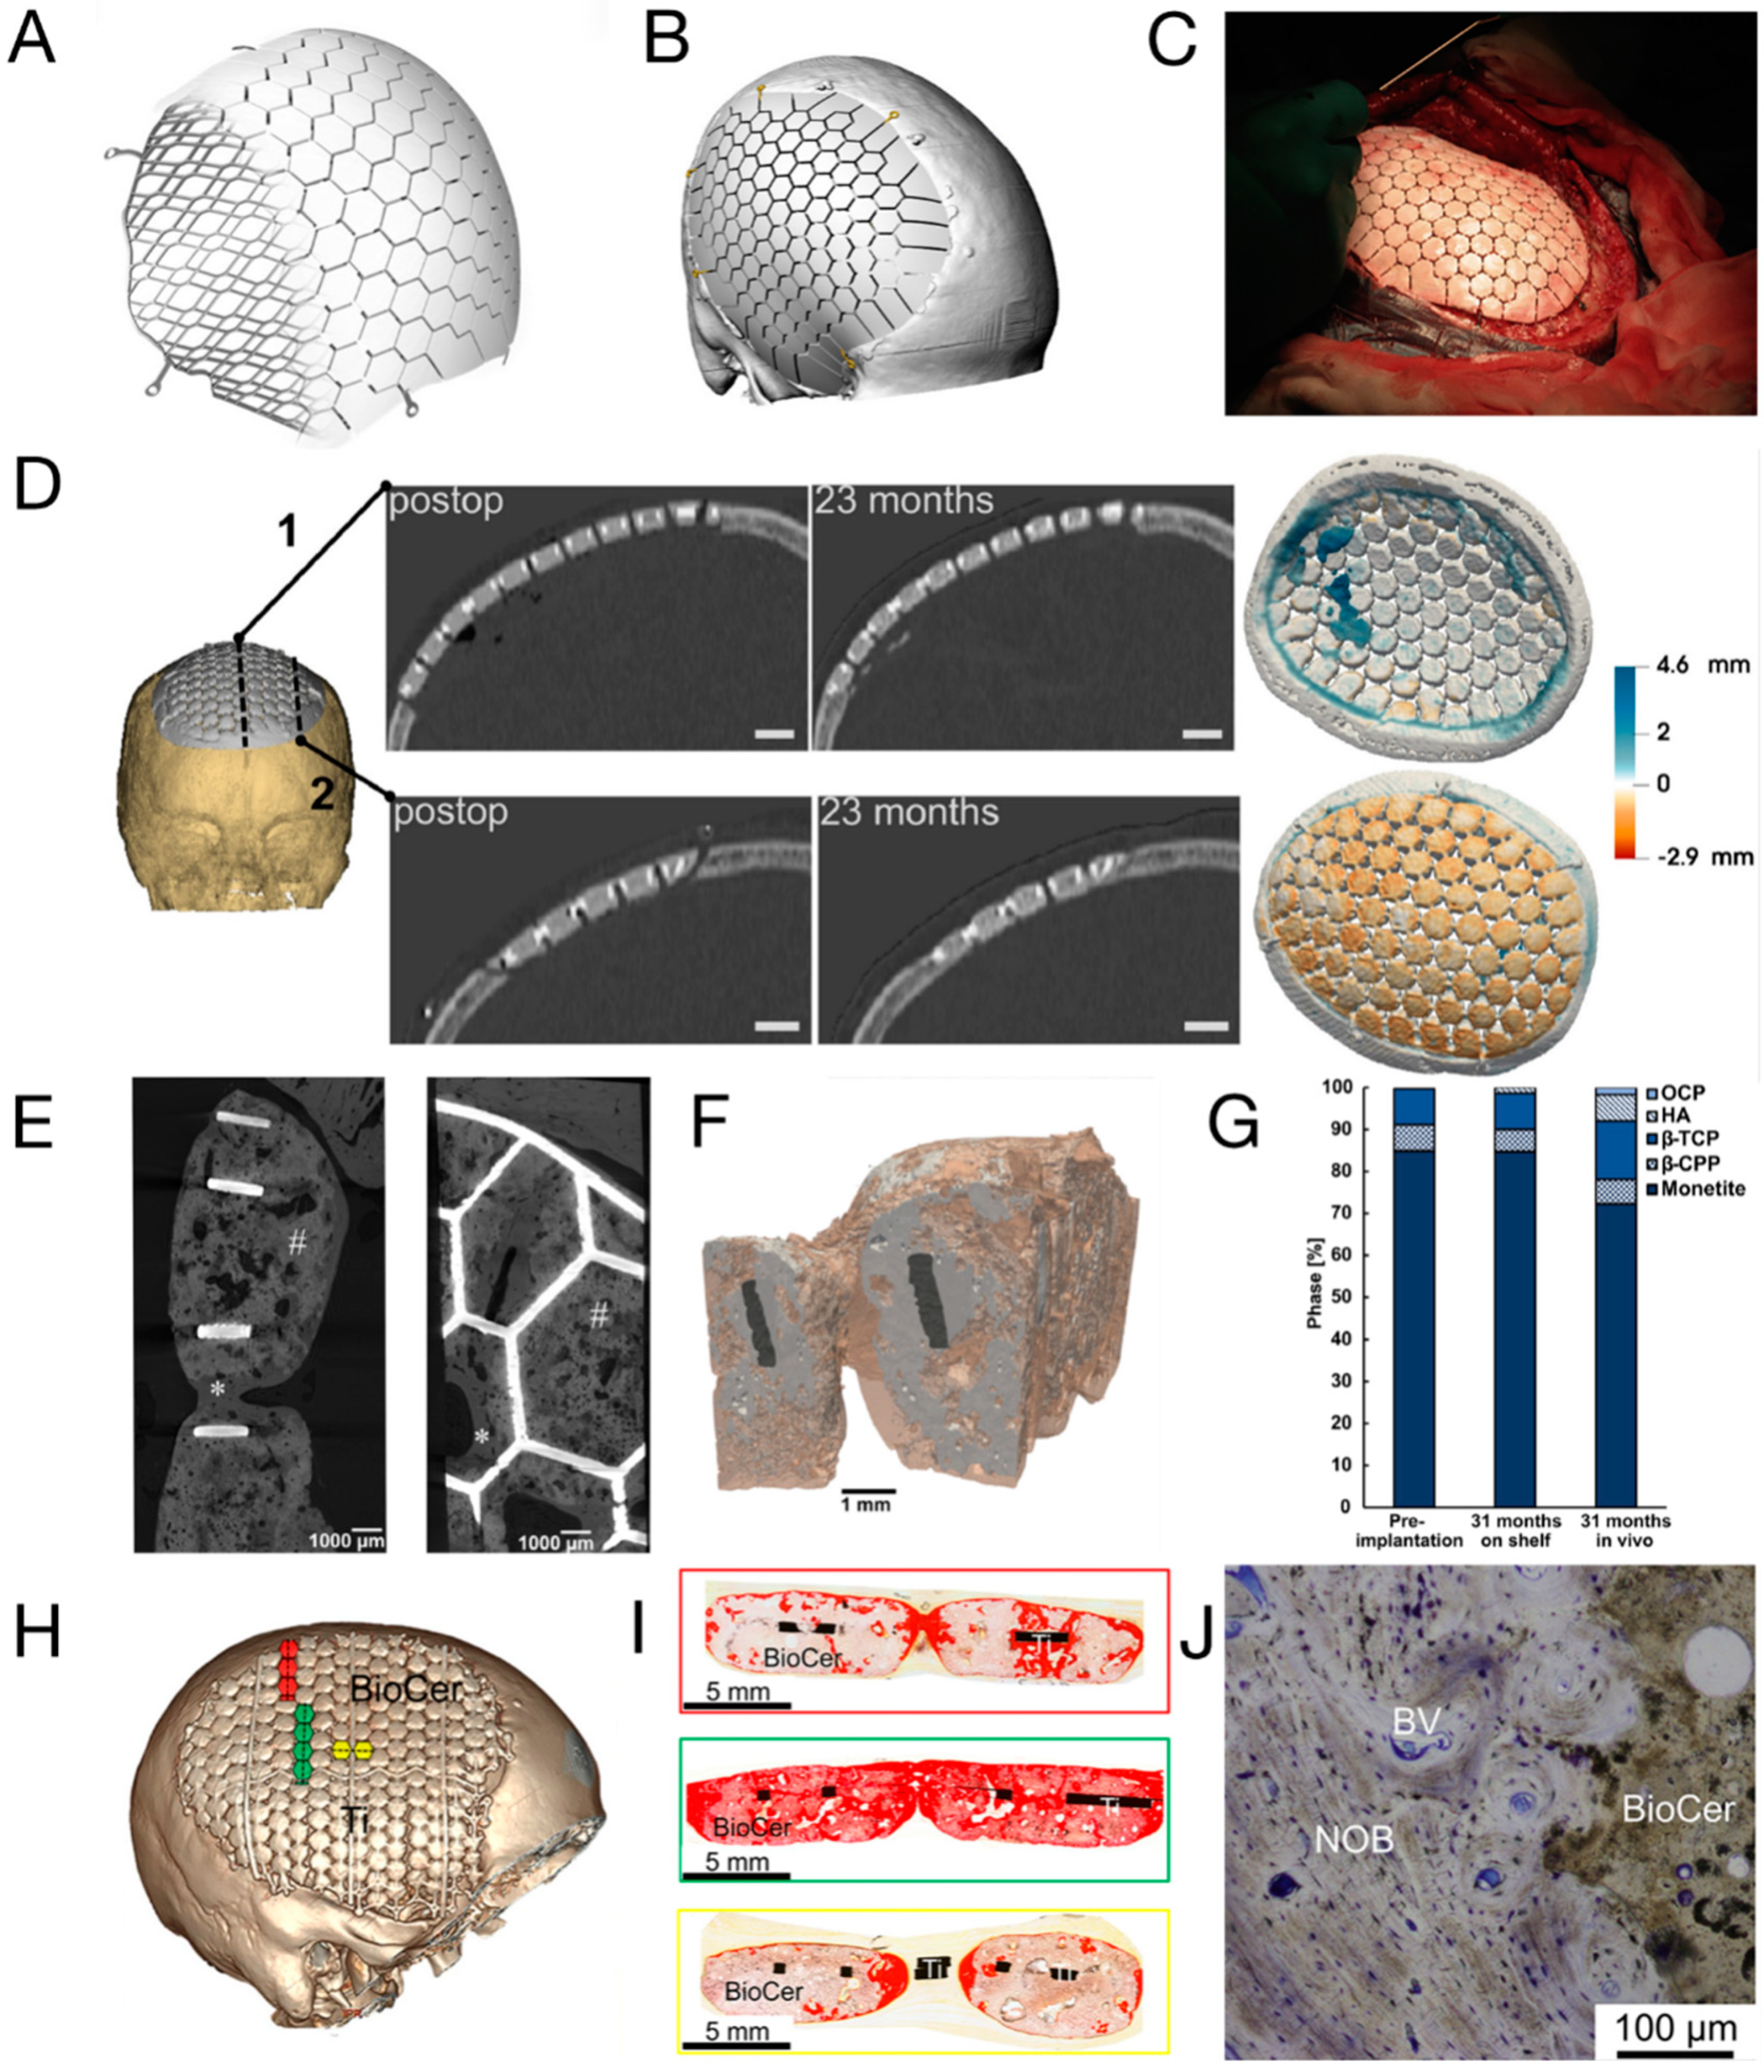

3.1. CaP/Ti Composites

- Omar, O.; Engstrand, T.; Kihlstrom Burenstam Linder, L.; Aberg, J.; Shah, F.A.; Palmquist, A.; Birgersson, U.; Elgali, I.; Pujari-Palmer, M.; Engqvist, H.; et al. In situ bone regeneration of large cranial defects using synthetic ceramic implants with a tailored composition and design. Proc. Natl. Acad. Sci. USA 2020, 117, 26660–26671. [Google Scholar] [CrossRef] [PubMed]

- Lewin, S.; Aberg, J.; Neuhaus, D.; Engqvist, H.; Ferguson, S.J.; Ohman-Magi, C.; Helgason, B.; Persson, C. Mechanical behaviour of composite calcium phosphate-titanium cranial implants: Effects of loading rate and design. J. Mech. Behav. Biomed. Mater. 2020, 104, 103701. [Google Scholar] [CrossRef] [PubMed]

- Gallinetti, S.; Linder, L.K.B.; Aberg, J.; Illies, C.; Engqvist, H.; Birgersson, U. Titanium reinforced calcium phosphate improves bone formation and osteointegration in ovine calvaria defects: A comparative 52 weeks study. Biomed. Mater. 2021, 16, 035031. [Google Scholar] [CrossRef] [PubMed]

- Lewin, S.; Fleps, I.; Åberg, J.; Ferguson, S.J.; Engqvist, H.; Öhman-Mägi, C.; Helgason, B.; Persson, C. Additively manufactured mesh-type titanium structures for cranial implants: E-PBF vs. L-PBF. Mater. Des. 2021, 197, 109207. [Google Scholar] [CrossRef]

- Kihlstrom Burenstam Linder, L.; Birgersson, U.; Lundgren, K.; Illies, C.; Engstrand, T. Patient-Specific Titanium-Reinforced Calcium Phosphate Implant for the Repair and Healing of Complex Cranial Defects. World Neurosurg. 2019, 122, e399–e407. [Google Scholar] [CrossRef]

- Sundblom, J.; Xheka, F.; Casar-Borota, O.; Ryttlefors, M. Bone formation in custom-made cranioplasty: Evidence of early and sustained bone development in bioceramic calcium phosphate implants. Patient series. J. Neurosurg. Case Lessons 2021, 1, CASE20133. [Google Scholar] [CrossRef] [PubMed]

- Bloom, O.; Goddard, N.; Yannoulias, B.; Eccles, S. The successful use of a bespoke OssDsign cranial plate to reconstruct an occipital defect following excision of a recurrent epithelioid sarcoma. JPRAS Open 2020, 24, 71–76. [Google Scholar] [CrossRef] [PubMed]

- Lewin, S.; Kihlstrom Burenstam Linder, L.; Birgersson, U.; Gallinetti, S.; Aberg, J.; Engqvist, H.; Persson, C.; Ohman-Magi, C. Monetite-based composite cranial implants demonstrate long-term clinical volumetric balance by concomitant bone formation and degradation. Acta Biomater. 2021, 128, 502–513. [Google Scholar] [CrossRef] [PubMed]

- Zhou, H.; Yang, L.; Gbureck, U.; Bhaduri, S.B.; Sikder, P. Monetite, an important calcium phosphate compound-Its synthesis, properties and applications in orthopedics. Acta Biomater. 2021, 127, 41–55. [Google Scholar] [CrossRef] [PubMed]

- Habibovic, P.; Gbureck, U.; Doillon, C.J.; Bassett, D.C.; van Blitterswijk, C.A.; Barralet, J.E. Osteoconduction and osteoinduction of low-temperature 3D printed bioceramic implants. Biomaterials 2008, 29, 944–953. [Google Scholar] [CrossRef] [PubMed]

- Pujari-Palmer, M.; Pujari-Palmer, S.; Lu, X.; Lind, T.; Melhus, H.; Engstrand, T.; Karlsson-Ott, M.; Engqvist, H. Pyrophosphate Stimulates Differentiation, Matrix Gene Expression and Alkaline Phosphatase Activity in Osteoblasts. PLoS ONE 2016, 11, e0163530. [Google Scholar] [CrossRef] [PubMed]

- Engstrand, T.; Kihlstrom, L.; Neovius, E.; Skogh, A.C.; Lundgren, T.K.; Jacobsson, H.; Bohlin, J.; Aberg, J.; Engqvist, H. Development of a bioactive implant for repair and potential healing of cranial defects. J. Neurosurg. 2014, 120, 273–277. [Google Scholar] [CrossRef] [PubMed]

- Engstrand, T.; Kihlström, L.; Lundgren, K.; Trobos, M.; Engqvist, H.; Thomsen, P. Bioceramic Implant Induces Bone Healing of Cranial Defects. Plast. Reconstr. Surg.-Glob. Open 2015, 3, e491. [Google Scholar] [CrossRef] [PubMed]